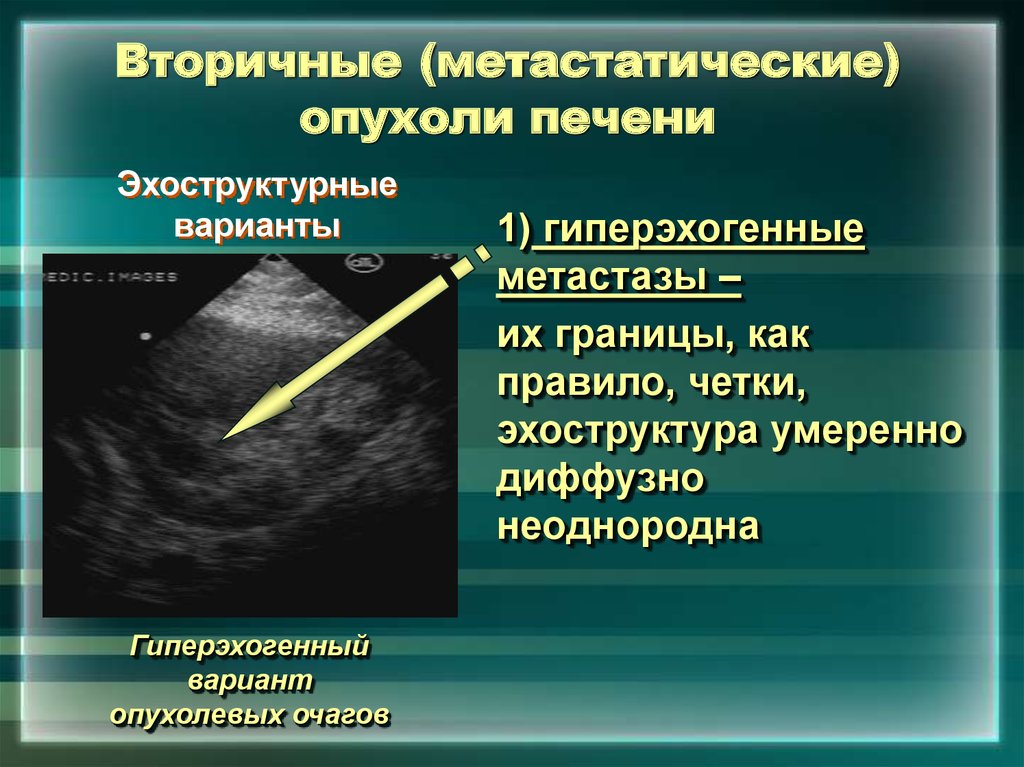

Метастатические поражения печени в ультразвуковом изображении характеризуются